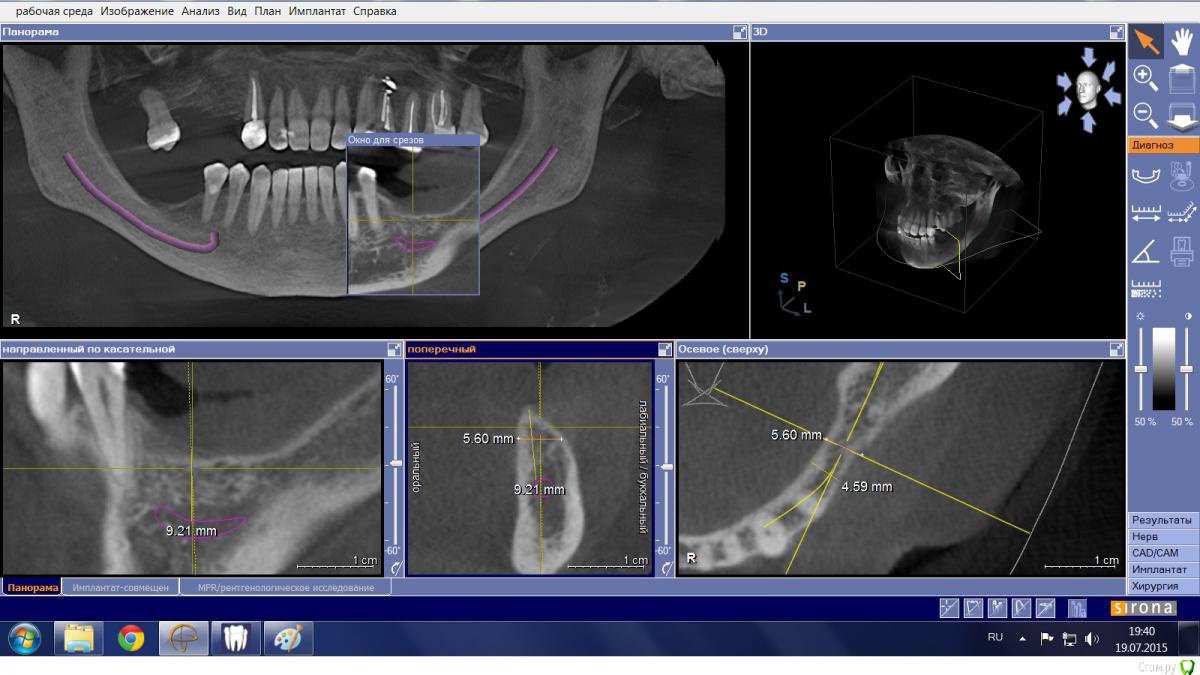

Mario Опубликовано 19 июля, 2015 Поделиться Опубликовано 19 июля, 2015 Здравствуйте, доктора, есть пациентка, категорически не желающая носить съемный протез и опыта такого не имеющая. Думал в сторону "крыши", но тут где-то ILGAMSA, кажется, писал, что не менее 5 мм крыша + 1 мм до канала, иначе резорбция. Латерализацию не рассматривал ввиду отсутствия соответствующего скилла. Какие еще могут быть варианты? Ссылка на комментарий

Mario Опубликовано 19 июля, 2015 Автор Поделиться Опубликовано 19 июля, 2015 Лучше отвертикалитьширина гребня в области 35 позволит? Ссылка на комментарий